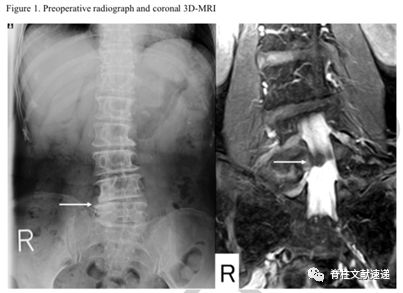

再手术后资料